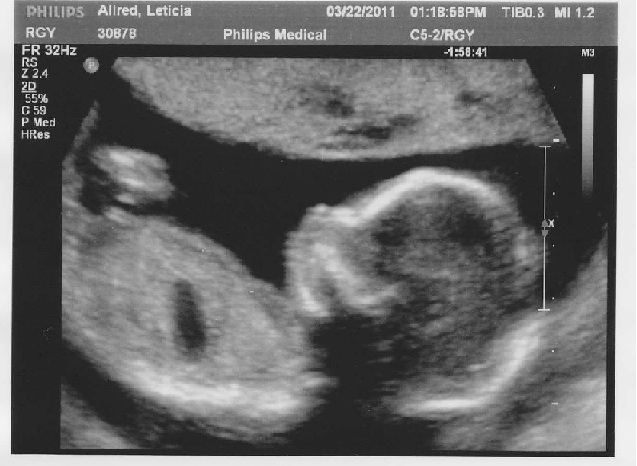

We are having a...

GIRL!

We will now have 3 wonderful little girls.